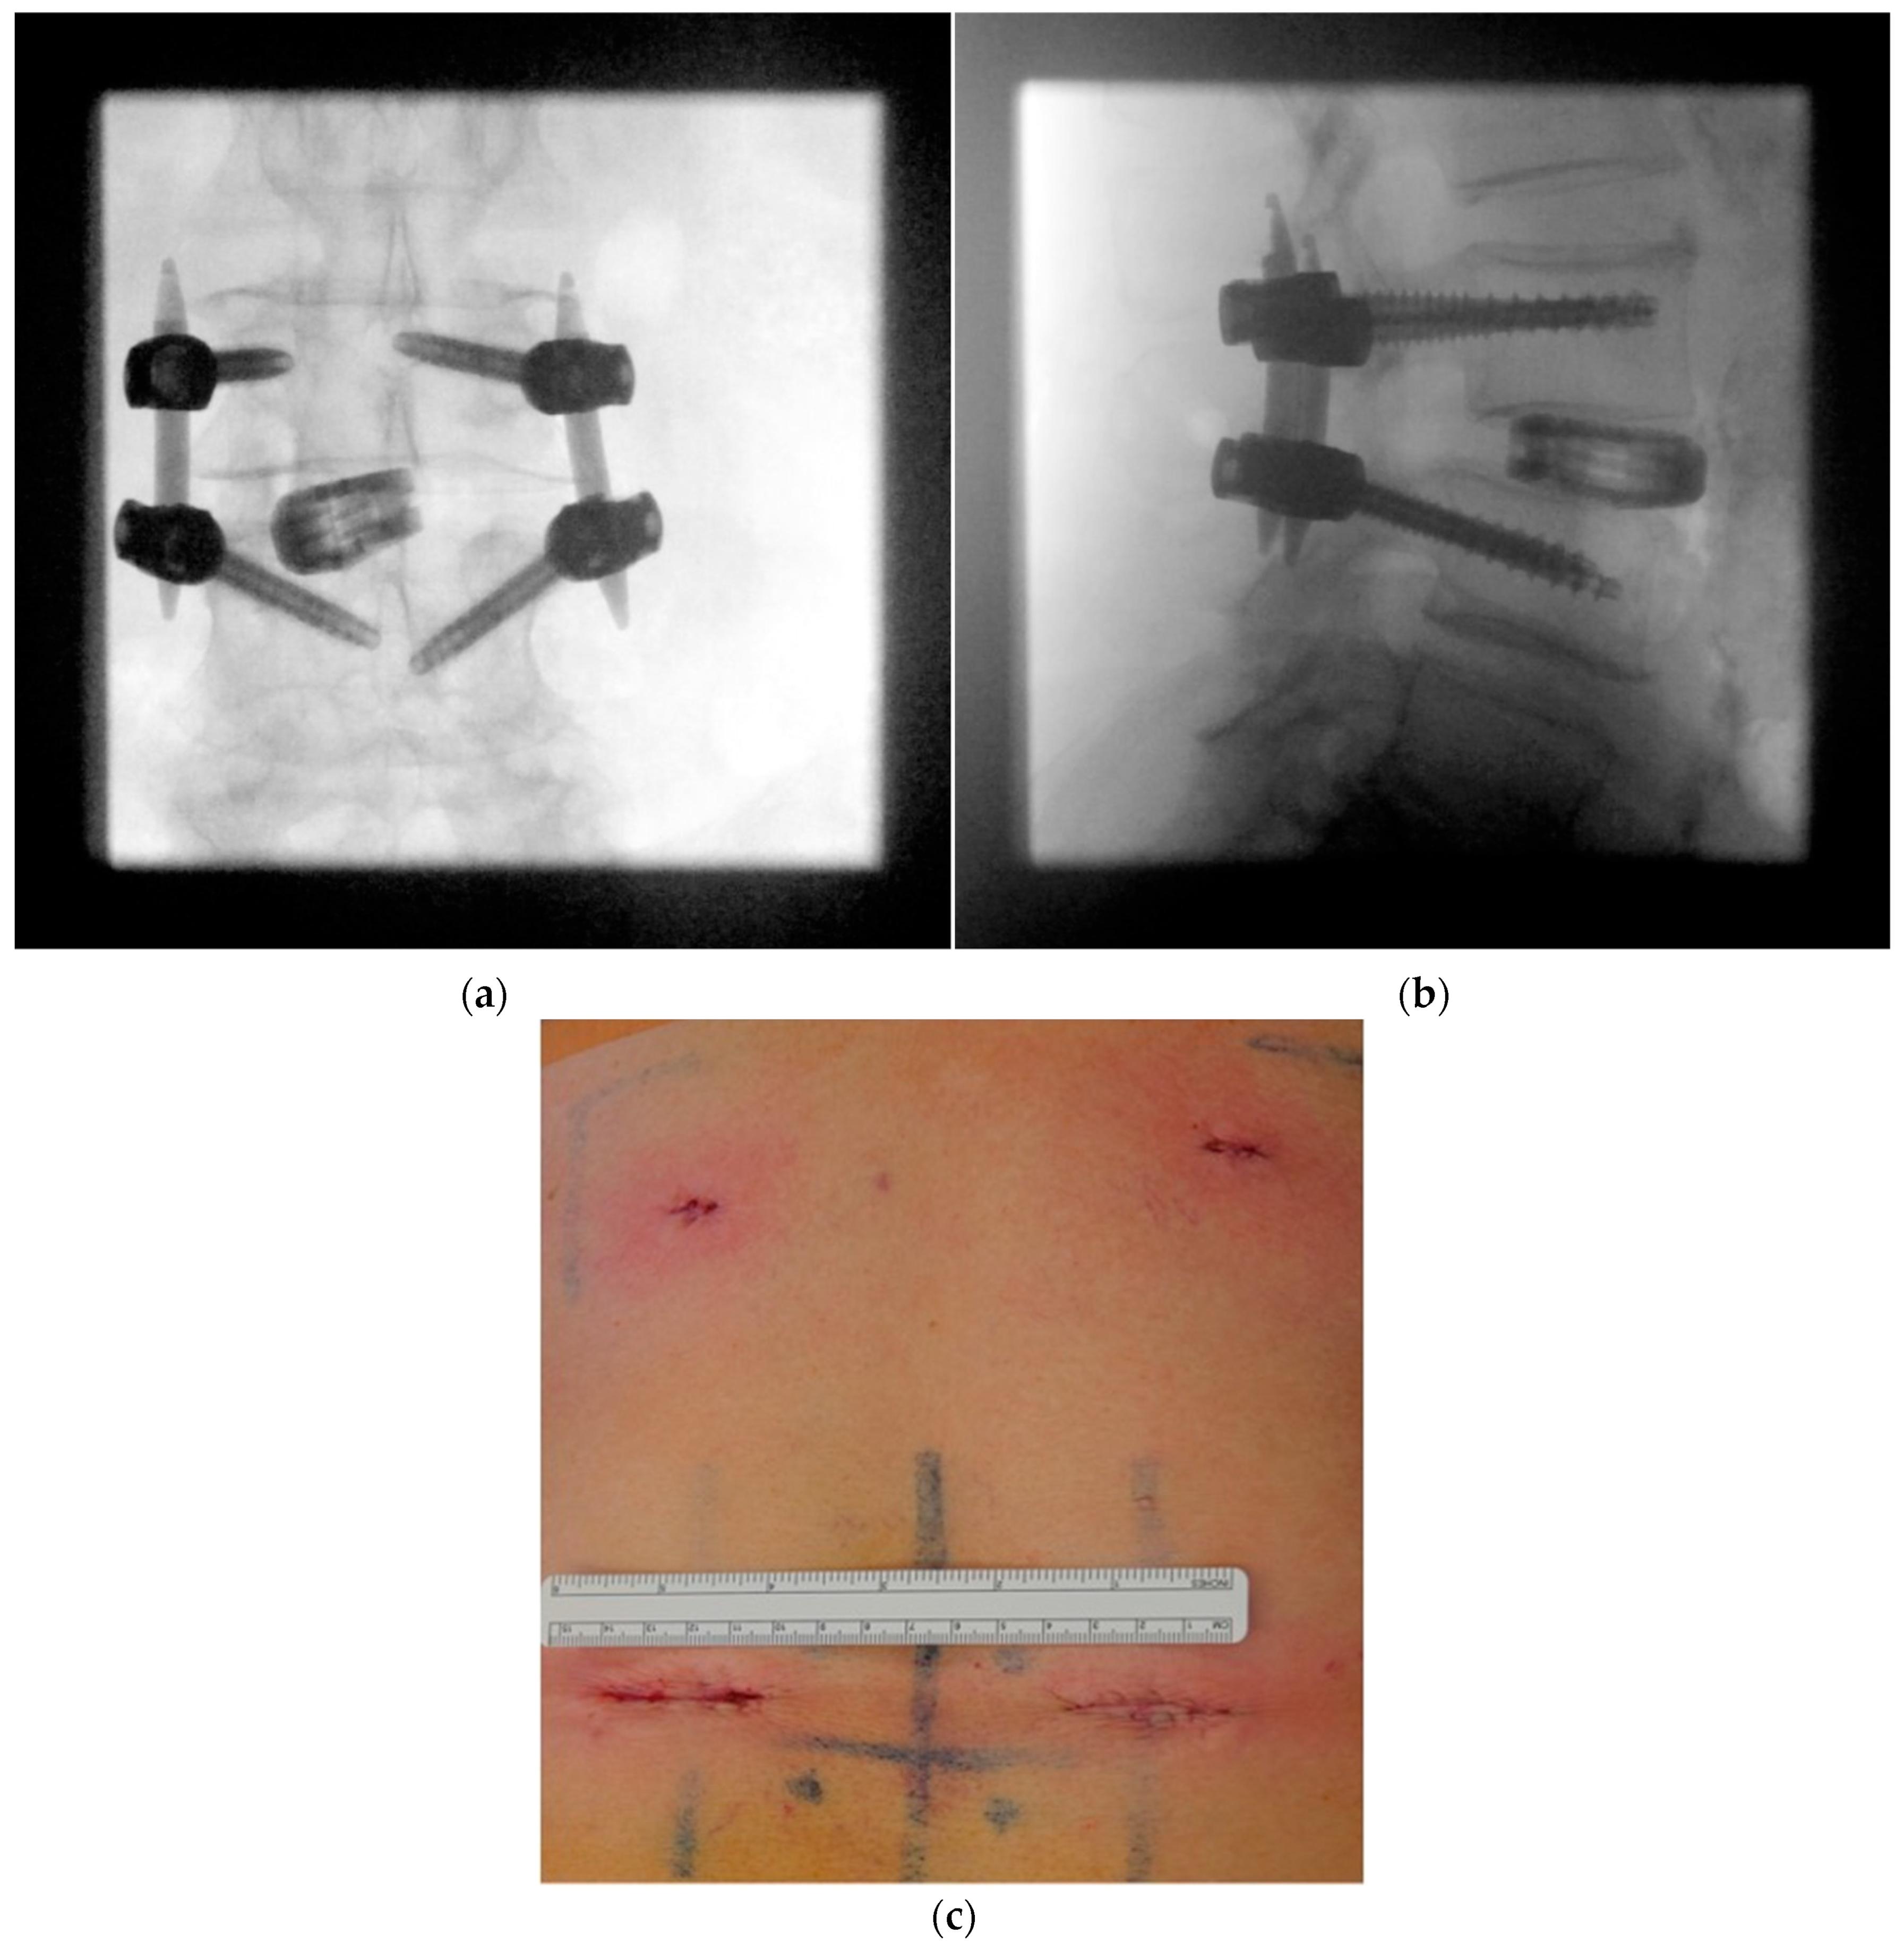

2.2. Radiation-Sparing Surgical Protocol

- Precise preoperative planning of screw trajectories and screw dimensions

- Using a metal template for entry point identification

- Jamshidi needle positioning and K-wire placement

- Confirmation of strictly transpedicular K-wire positioning

- Ipsilateral placement of a tubular non-expandable retractor

- Pedicle screw insertion

- Facetectomy, decompression, discectomy, and distraction

- Cage placement under lateral radiographic control

- Ipsilateral screw placement usually without imaging

- MIS rod insertion using haptic feedback and no or very sparse lateral radiographic control